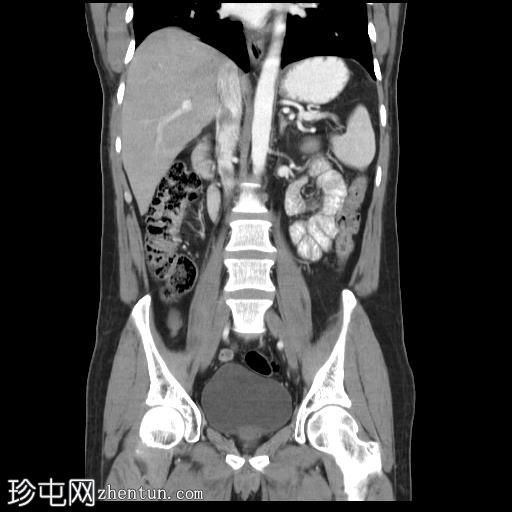

冠状位增强扫描(口服造影剂)

冠状位增强扫描(门静脉期)

CT扫描显示胰腺组织完全包绕十二指肠第二段。未发现胰周结节或肿块。

左肝III段可见一低密度囊肿,直径约15 mm。

此外,右肝VII段可见一低密度病灶,呈结节状强化,直径达12 mm,提示肝血管瘤。

左肝II段可见一强化病灶,提示快速充盈型血管瘤。

此外,肝实质内可见少量低密度病灶,但体积过小,无法准确定性。

环状胰腺是一种形态学异常,其特征是胰腺组织完全或部分环绕十二指肠第二段。这种情况可导致十二指肠梗阻,因此放射科医生识别此病至关重要,因为他们通常是第一个提出诊断的医生。